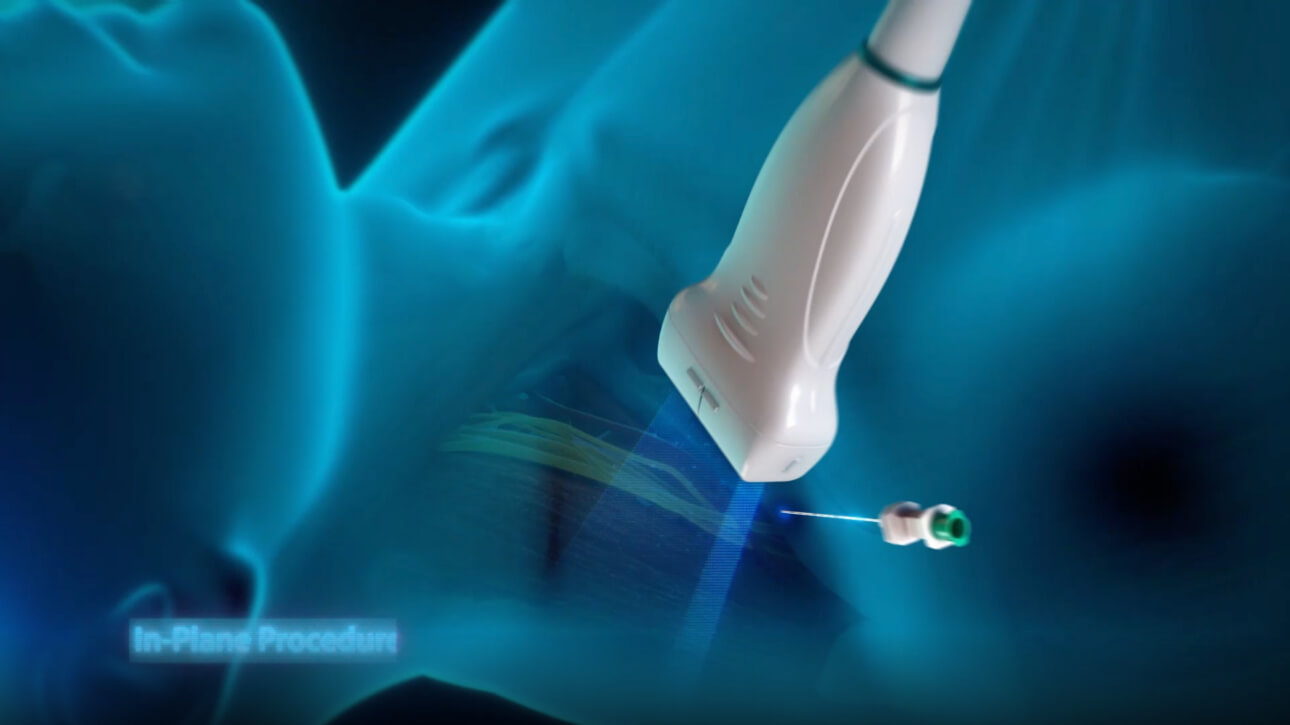

Esforzarse por una mejor atenciĂłn al paciente y buscar la mejor soluciĂłn para una decisiĂłn rĂĄpida es esencial para el personal clĂnico. Con herramientas inteligentes de gestiĂłn de fluidos, funciones para punciones seguras, una soluciĂłn completa de desinfecciĂłn e imĂĄgenes de calidad superior, el equipo Mindray TE7 ACE estĂĄ dise?ado para cubrir las aplicaciones de anestesia, cuidados crĂticos y emergencias. Listo para prestar atenciĂłn en cualquier momento, fĂĄcil de aprender y usar, ayuda a enfrentar con confianza todos los desafĂos de los servicios mĂ©dicos de alta calidad. Por primera vez, el TE7 ACE como ecĂłgrafo puede conectarse sin problemas a su red clĂnica con todos los demĂĄs equipos.